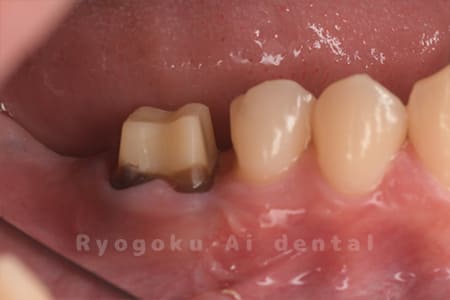

Case14

-

- 抜歯原因

- 重度カリエス

- 治療内容

- クラウンレングスニング治療

- 治療費用

- 44,000円

他院で抜歯と言われた、とのことでご来院された患者さまです。クラウンレングスニングを行い、保存致しました。大変満足して頂けました。